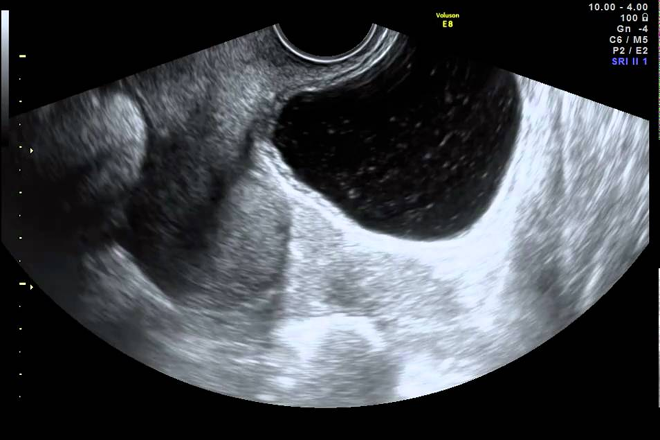

Miomatosis Uterina

Su representación morfológica consiste en au­mento de las dimensiones del útero, con pérdida de la homogeneidad de la ecogenicidad uterina y en ocasiones la ondulación del contorno del útero.

Los leiomiomas son las neoplasias más frecuentes del útero, Es la cau­sa más común de aumento del tamaño del útero ante la ausencia de gestación.

Estos tumores benignos cursan asin­tomáticos. Su localización puede ser intramural (miometriales), subserosos (superficie peritoneal del útero) o submucosos (proyección intracavi­taria).

En la práctica ultrasonográfica, los hallazgos de miomatosis, como ya se mencionó, consisten en aumento de tamaño del útero, usualmente a expensas de su diámetro anteroposterior (20-30% de aumento), heterogeneidad de la ecogenicidad uterina y contorno ondulado por la presencia de miomatosis subserosa. Los miomas submucosos alteran el aspecto del endometrio, deformándolo y modificando su ecogenicidad.